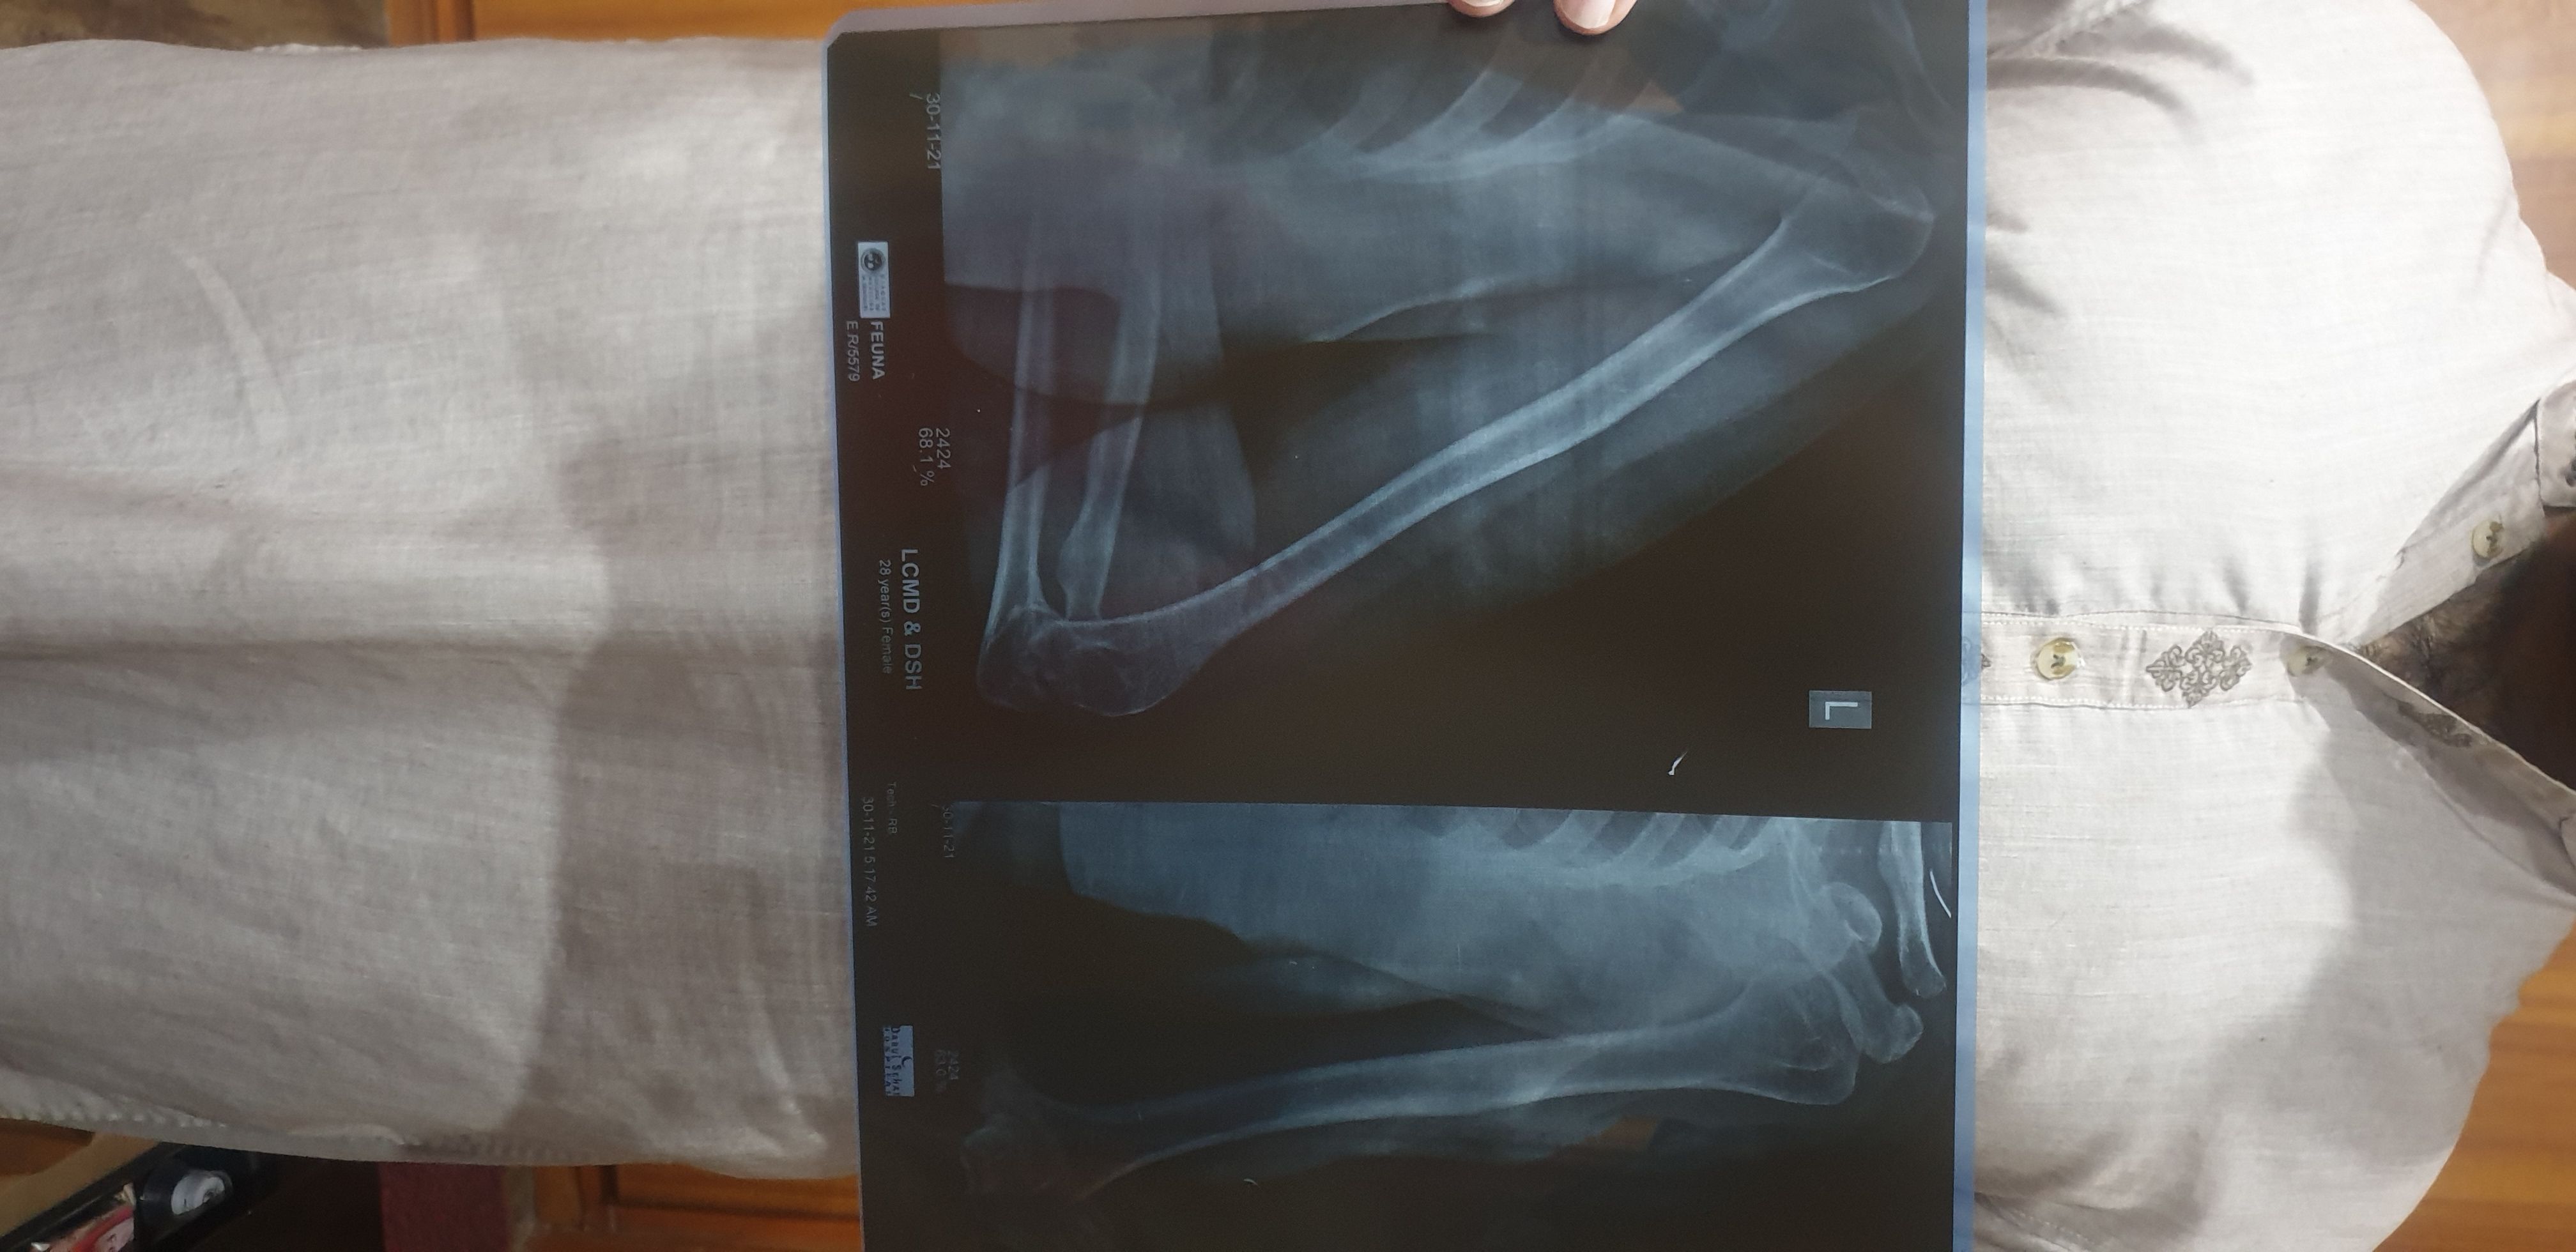

upload your medications plus x ray.

agar just dard ha tu dard ke lye painkillers ap konse le rahe ho?

xray

4 years ago

Member

Post Owner

ex ray